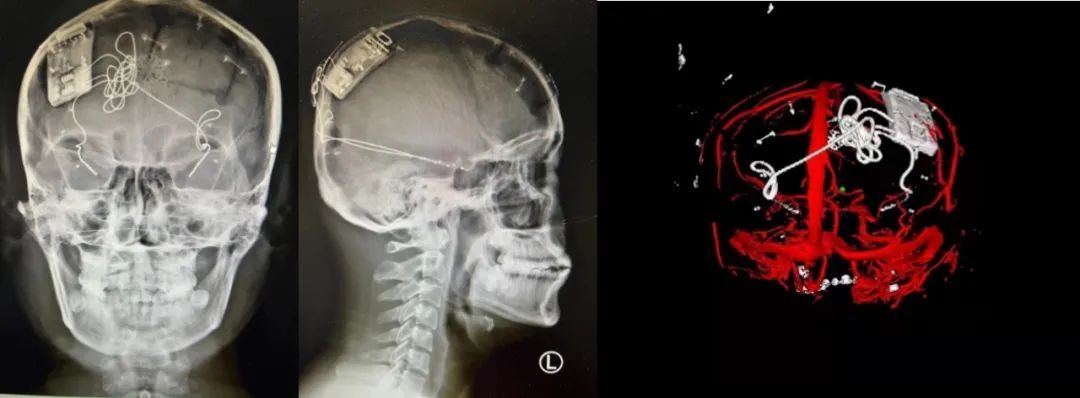

本次手術過程順利,術中刺激器各項指標均工作正常,術后重建顯示電極位置精準,腦電信號清晰?;颊邽槟行?,入院后診斷為雙側顳葉癲癇,此類癲癇為開顱手術的相對禁忌癥,在藥物無法控制的情況下,傳統(tǒng)治療效果欠佳 。

術前經(jīng)過宣武醫(yī)院癲癇多學科專家團隊詳細的臨床評估,包括視頻腦電監(jiān)測、頭顱磁共振及三維 CT 掃描、腦核醫(yī)學檢查等,全面評估了患者病情及致癇灶定位情況。

由于患者臨床診斷為雙側顳葉癲癇伴海馬硬化,無法通過致癇灶切除等傳統(tǒng)外科手術方式獲益,決定進行閉環(huán)反應性神經(jīng)刺激系統(tǒng)植入手術治療。并根據(jù)閉環(huán)神經(jīng)刺激技術特點,為患者“量身定制”植入方案,尤其是電極植入位點和脈沖發(fā)生器固定部位等,為手術的順利實施奠定了良好基礎。

團隊根據(jù)術前計劃,在手術機器人輔助下完成雙海馬長軸電極及 IPG 植入,術后重建顯示電極位置精準,腦電信號清晰。術后第二天,患者即下床活動,身體狀況恢復良好。